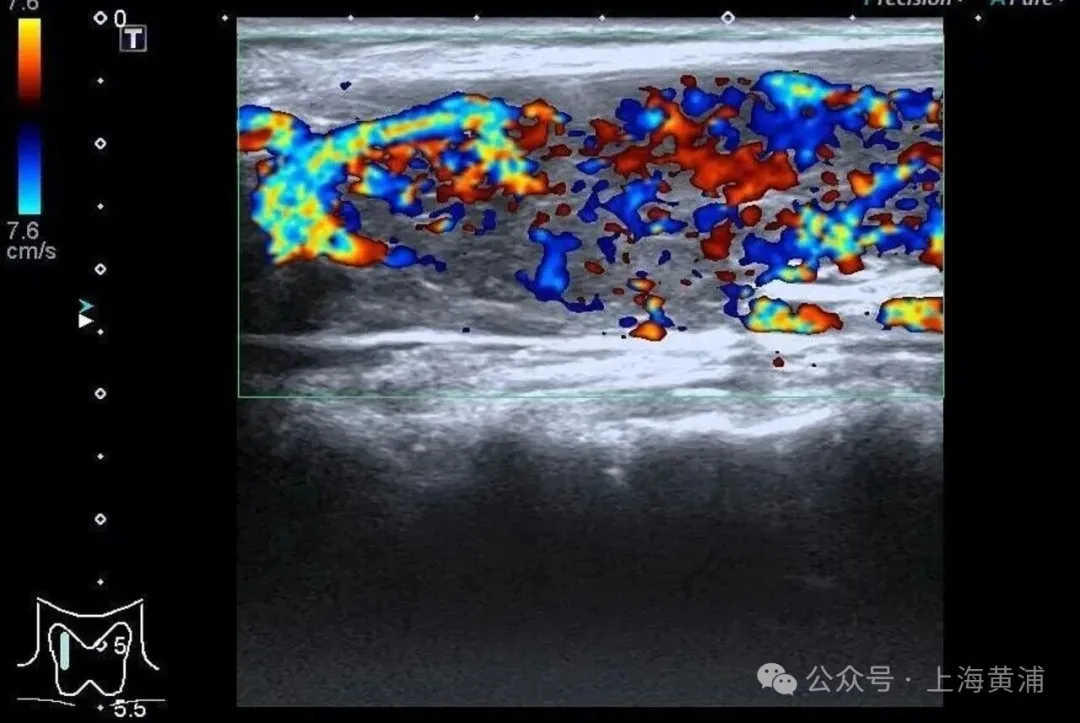

住院后的检查闭幕泄露

陈女士的体魄

正被一场“激素风暴”席卷

甲状腺功能检查中,游离T3高达20.83 pmol/L(平方值3.5 - 6.5pmol/L),游离T4高达88.42 pmol/L(平方值11.5 - 22.7pmol/L),这两项中枢激素齐逾越平方上限数倍,而本应调控它们的促甲状腺激素(TSH)却险些测不出来,这明确阐明了陈女士患有极其严重的甲状腺毒症。腹黑超声闭幕相同辞谢乐不雅,射血分数仅有40%(平方应高于55%),这意味着腹黑泵血才略大幅下跌。